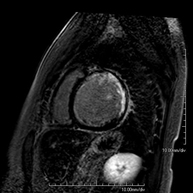

És una prova diagnòstica no invasiva que obté informació morfològica i funcional del cor i les estructures adjacents. D'aquesta manera es poden diagnosticar diferents patologies congènites i adquirides, o bé realitzar controls en pacients amb patologia prèvia ja coneguda. En la gran majoria de casos és necessari l'ús de contrast intravenós (Gadolini) per completar l'estudi, un tipus de contrast que rarament produeix reaccions adverses. Durant la prova el tècnic li demanarà diverses vegades que aguanti la respiració durant 10-15 segons per obtenir les imatges tant clares sigui possible. No es necessita preparació prèvia per part del pacient. La durada de la prova és de 45 – 60 aproximadament. Està contraindicada en pacients amb marcapassos. El pacient haurà d'avisar en cas que porti implants metàl·lics i/o clips quirúrgics. - RM cardíaca amb estrès miocardi

És una prova diagnòstica no invasiva que obté informació morfològica i funcional del cor i les estructures adjacents. D'aquesta manera es poden diagnosticar diferents patologies congènites i adquirides i realitzar controls en pacients amb patologia prèvia ja coneguda. En la majoria de casos és necessari l'ús de contrast intravenós (Gadolini) per completar l'estudi, un tipus de contrast que estranyament produeix reaccions adverses. Durant la prova el tècnic li demanarà diverses vegades que aguanti la respiració durant 10-15 segons per obtenir les imatges el més clares possible. No requereix preparació prèvia per part del pacient. La durada de la prova és d'aproximadament 45-60 minuts. Està contraindicada en pacients amb marcapassos i el pacient ha d'indicar si és portador d'implants metàl·lics i/o clips quirúrgics. - RM Cardíaca amb estrès miocàrdic

És una prova diagnòstica no invasiva que obté informació morfològica i funcional del cor i les estructures adjacents. D'aquesta manera es poden diagnosticar diferents patologies congènites i adquirides. Durant la prova el tècnic li demanarà diverses vegades que aguanti la respiració durant 10-15 segons per poder obtenir les imatges el més clares possible. En la gran majoria de casos és necessari l'ús de contrast intravenós (Gadolini) per completar l'estudi, un tipus de contrast que rarament produeix reaccions adverses. A més, s'introdueix un fàrmac (Adenosina) per via intravenosa, per exercir sobre el cor un efecte similar al que es produeix durant l'exercici físic. Es comparen les imatges obtingudes en repòs i després de "l'estrès" farmacològic per detectar dèficits d'aportació sanguini al ventricle esquerre del cor. La durada de la prova és d'aproximadament 45-60 minuts. El pacient no haurà d'ingerir aliments que continguin cafeïna durant les 24 hores prèvies a prova (cafè, te, xocolata, begudes de cola, etc.). Està contraindicada en pacients amb marcapassos i el pacient ha d'avisar si és portador d'implants metàl·lics i/o clips quirúrgics. - Angio-RM de Venes pulmonars